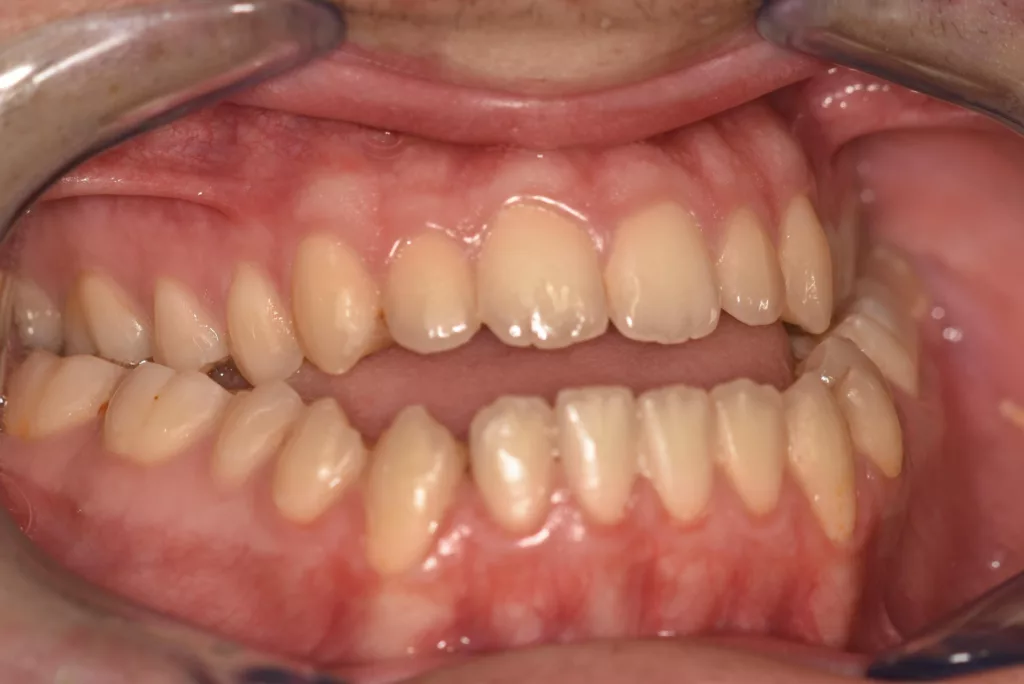

Principales malformations rencontrées : Les Classes II squelettiques

La mandibule est en retrait par rapport au maxillaire supérieur. Il peut s’agir d’un manque de développement de la mandibule et d’un maxillaire supérieur normal ou au contraire d’une mandibule normale et d’un maxillaire anormalement projeté vers l’avant. Parfois, les deux anomalies se conjurent associant un manque de développement de la mandibule et un maxillaire positionné trop en avant. Le profil facial classiquement observé est « convexe » ou « fuyant » tandis que l’on retrouve fréquemment une occlusion dentaire de classe II. L’appellation courante est le « rétrognathisme ».

Il existe de nombreuses variétés de Classe II squelettiques. Parmi les plus fréquentes, on distingue les Classe II squelettiques avec surplomb des incisives supérieures (Classes II Division 1) et les Classes II squelettiques avec recouvrement des incisives inférieures par les incisives supérieures (Classes II Division 2).

Classe II Squelettique Division 1 :

Classe II Squelettique Division 1

Classe II Squelettique Division 2 :

Classe II Squelettique Division 2